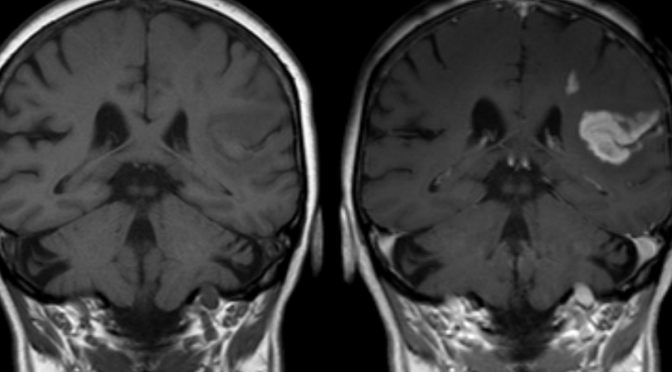

O AVC afeta as artérias cerebrais e dá-se «quando um vaso sanguíneo que transporta oxigénio e nutrientes para o cérebro rompe ou é bloqueado por um coágulo. Quando tal acontece, uma parte do cérebro não consegue obter o sangue e oxigénio de que necessita e começa a morrer», informa a American Heart Association (AHA). O acidente é súbito e os seus efeitos no organismo são imediatos. Existem essencialmente dois tipos de AVC, os isquémicos e os hemorrágicos. Os primeiros ocorrem quando um coágulo bloqueia uma artéria, impedindo a irrigação sanguínea de uma área do cérebro. Os segundos dão-se quando uma artéria rompe.

O cérebro controla as funções corporais em áreas específicas, pelo que as consequências dependem da área e extensão afetada. Se o AVC afetar a área (hemisfério esquerdo) que controla os movimentos do corpo do lado direito, esse lado vai ficar paralisado. O cérebro também controla os processos mentais mais nobres, como comunicar, sentir, pensar, que também podem ficar afetados.